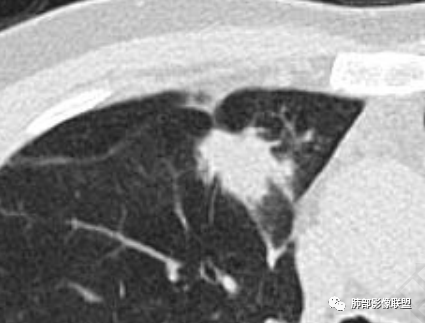

1.临床特点:52岁男性,体检发现肺结节。有吸烟史。非小细胞肺癌相关抗原与神经元烯醇化酶轻度升高。2.影像特点:右肺上叶前段可见不规则结节影,整体膨隆,可见浅分叶,周围局部可见边界清楚的磨玻璃影。可见血管集束征及脐凹征,临近叶间胸膜受牵拉凹陷,局部支气管到达病灶边缘后显示截断。3.病例小结:中老年吸烟男性,右肺上叶前段不规则结节,膨胀感较明显,收缩力强,支气管截断,加上边界清楚的磨玻璃影。符合浸润性腺癌表现。

5.具有收缩力表现:胸膜牵拉凹陷、兔耳征、毛刺征、纠集征等。

6.支气管充气征与支气管牵张扭曲。

8.膨胀边缘与胸膜处锐角。